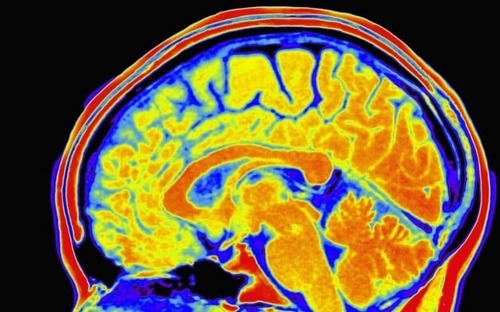

Intelligence could be measured with a swab of saliva, or drop of blood, after scientists showed for the first time that a person’s IQ can be predicted just by studying their DNA.